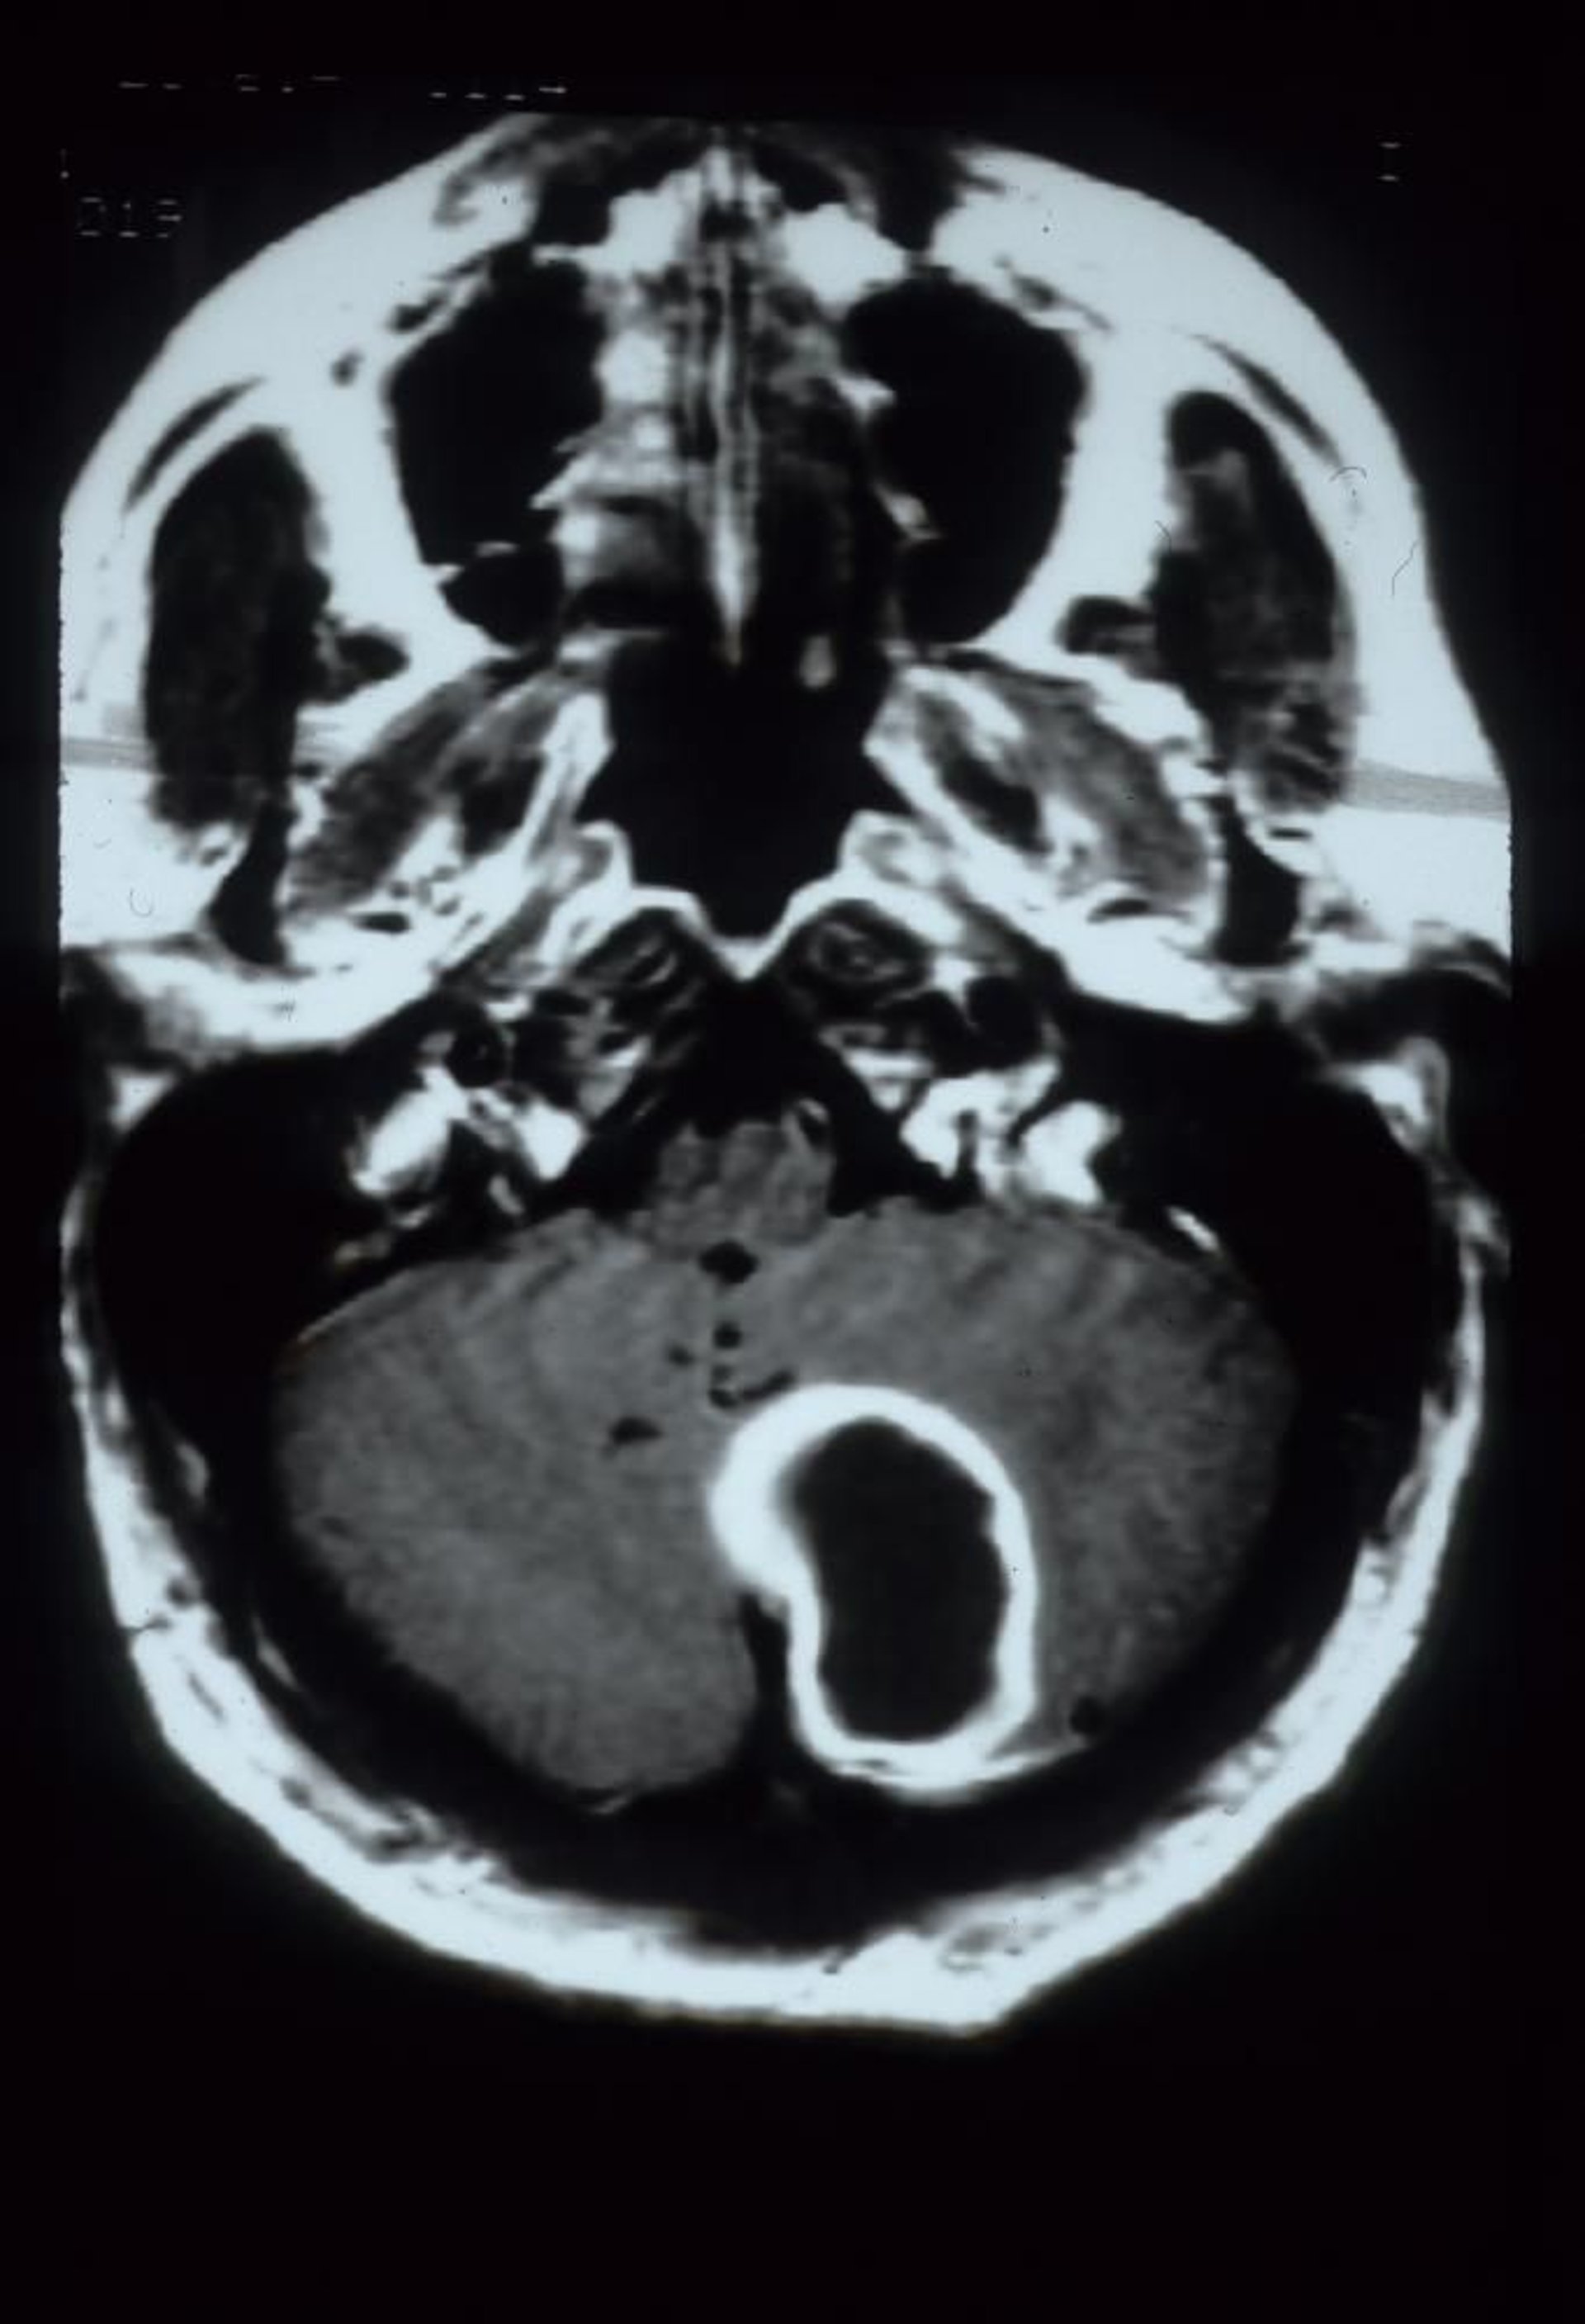

When symptoms suggest an abscess, contrast-enhanced MRI with diffusion-weighted images or, if MRI is unavailable, contrast-enhanced CT is done. A fully developed abscess appears as an edematous mass with ring enhancement, which may be difficult to distinguish from a brain tumor or occasionally infarction; CT-guided aspiration, culture, surgical excision, or a combination may be necessary.

This gadolinium-enhanced MRI scan shows a cerebellar abscess, which appears as a large, rim-enhancing cavitary lesion in the left cerebellar hemisphere.

Courtesy of John E. Greenlee, MD.